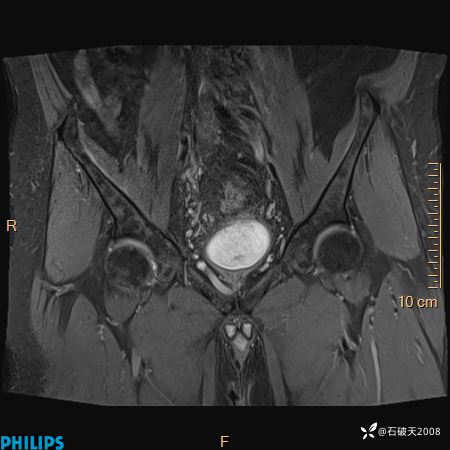

2023年3月份MRI影像

T2压脂冠状位